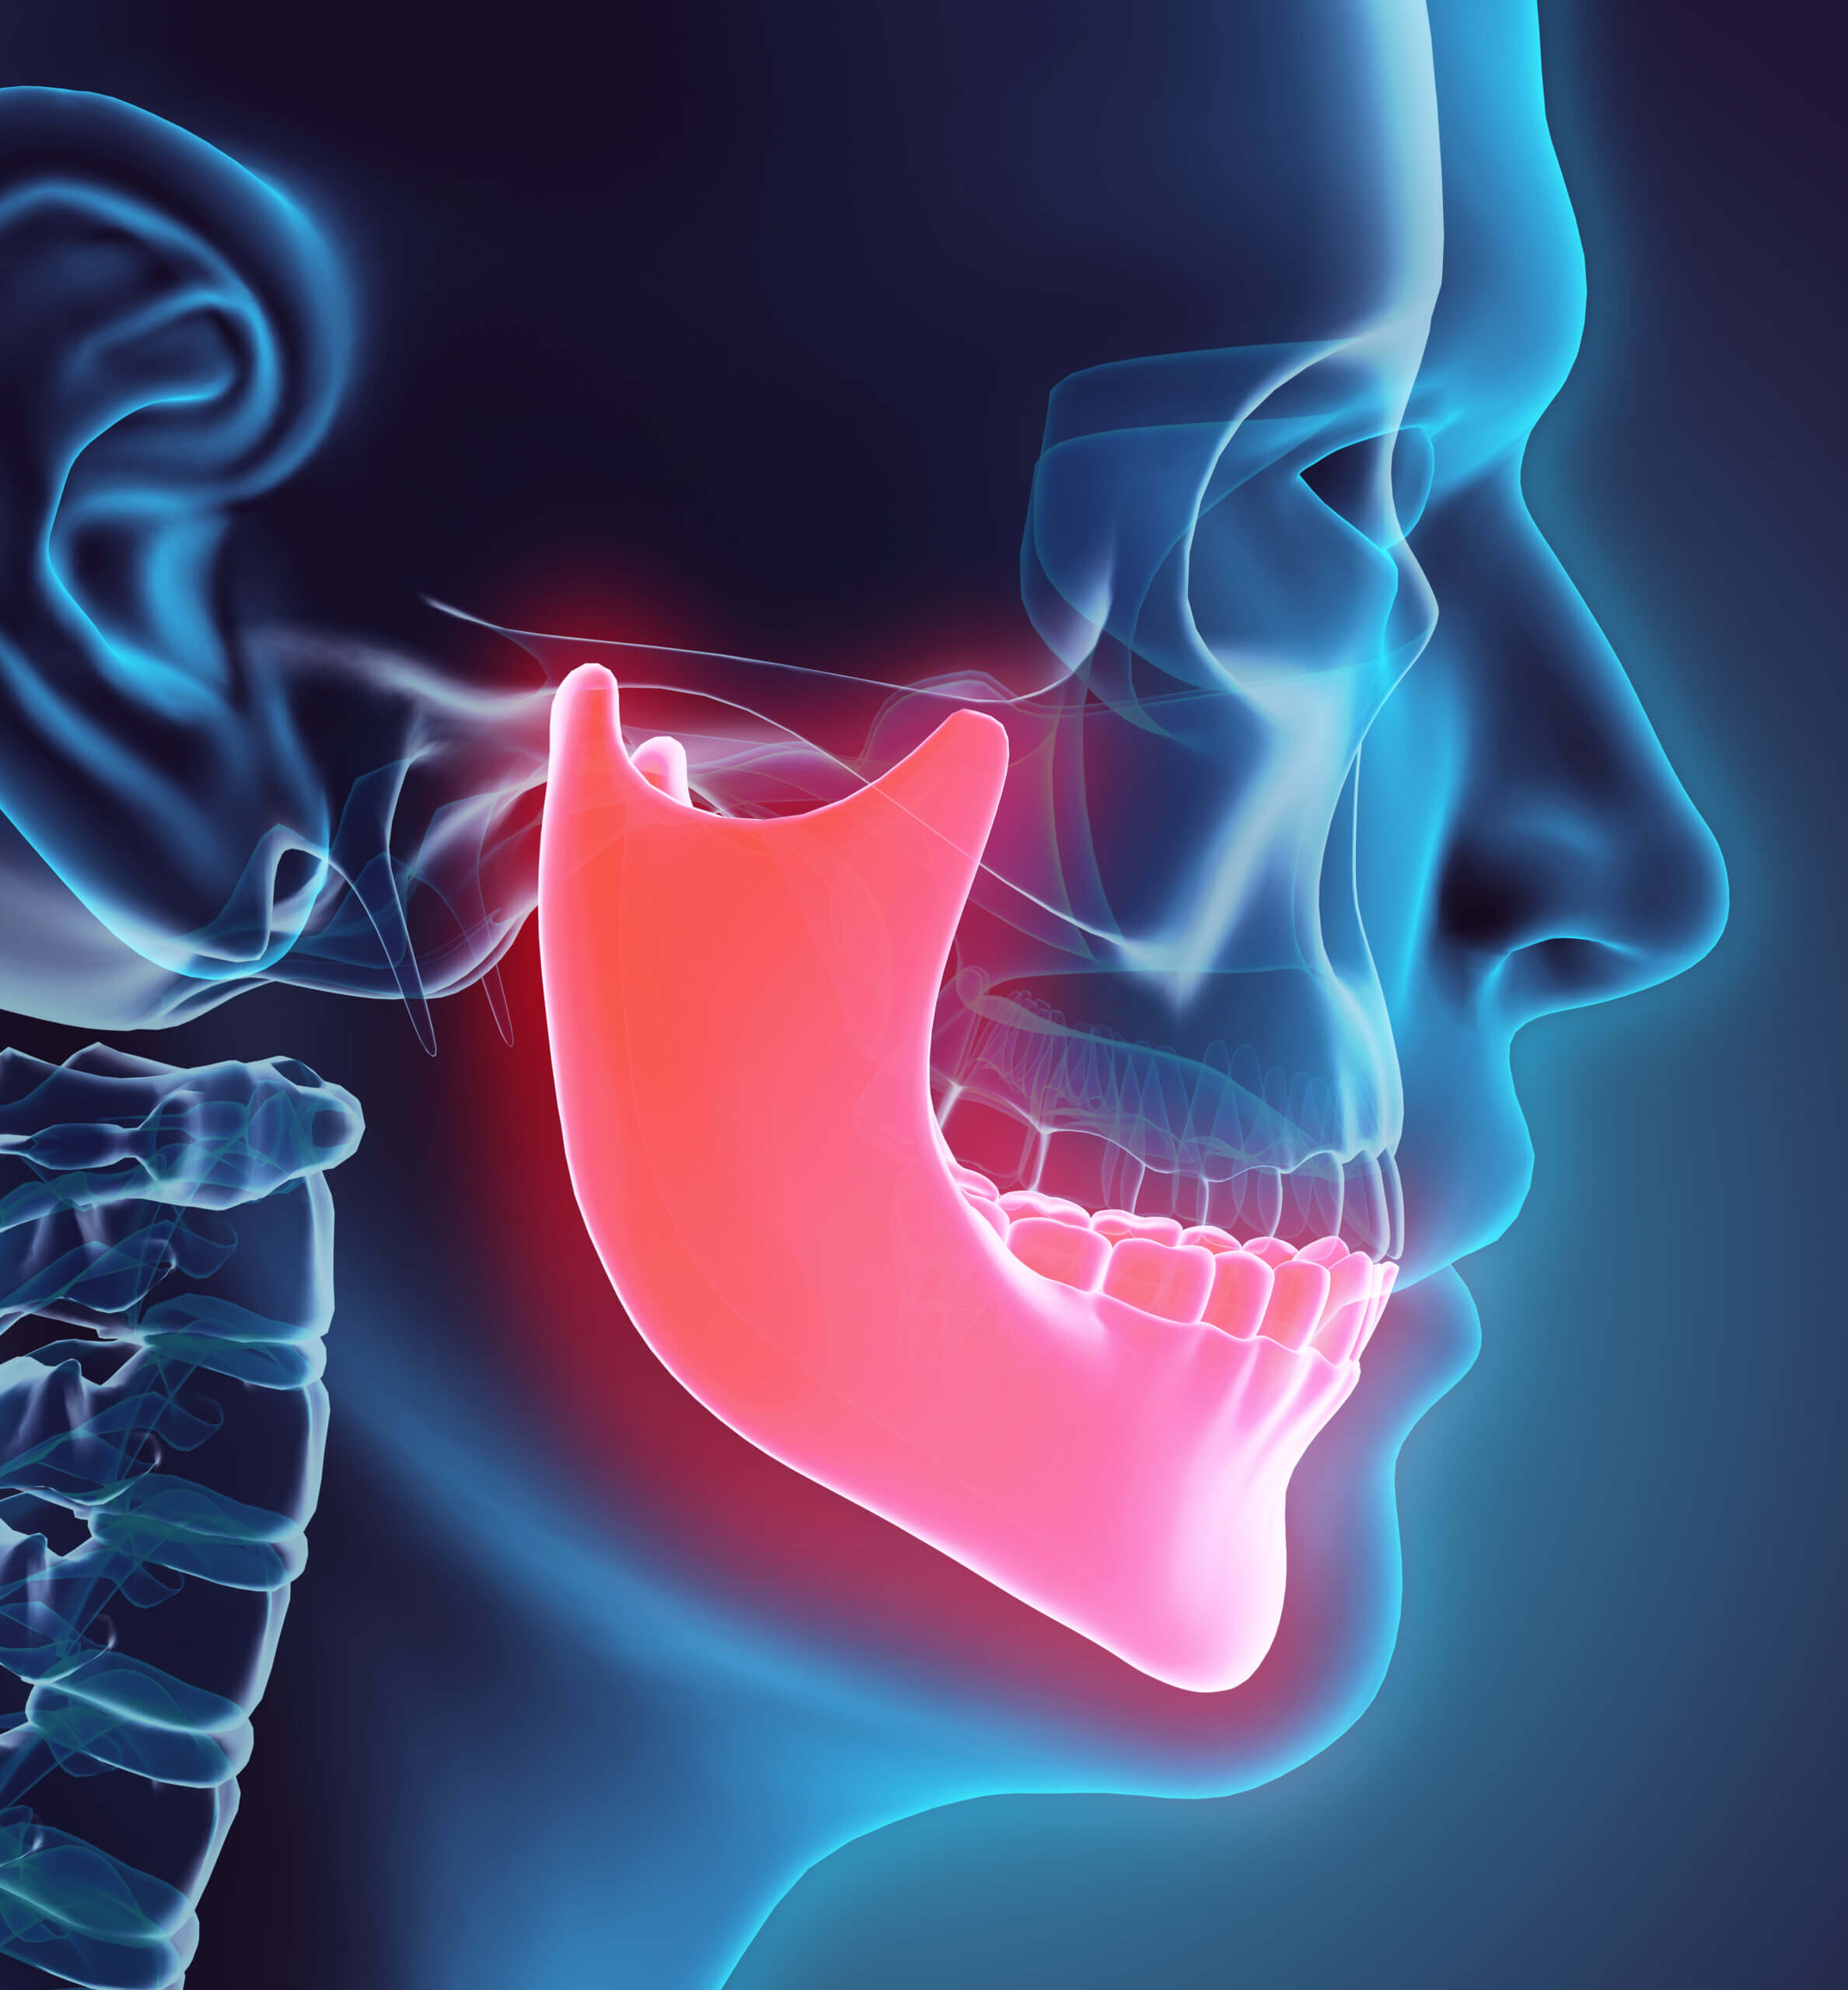

Osteonecrosis of the Jaw

Osteonecrosis of the Jaw Osteonecrosis is death of the bone tissue in some portions of the jaw. This condition indicates that portions of the bone is no longer live tissue. [...]